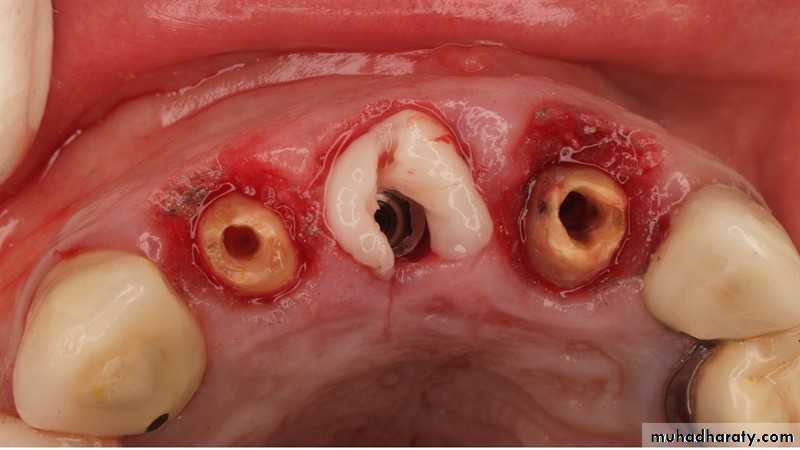

Gingival management

• Retraction cord• Gingivectomy

• Laser

• Electro-cautery